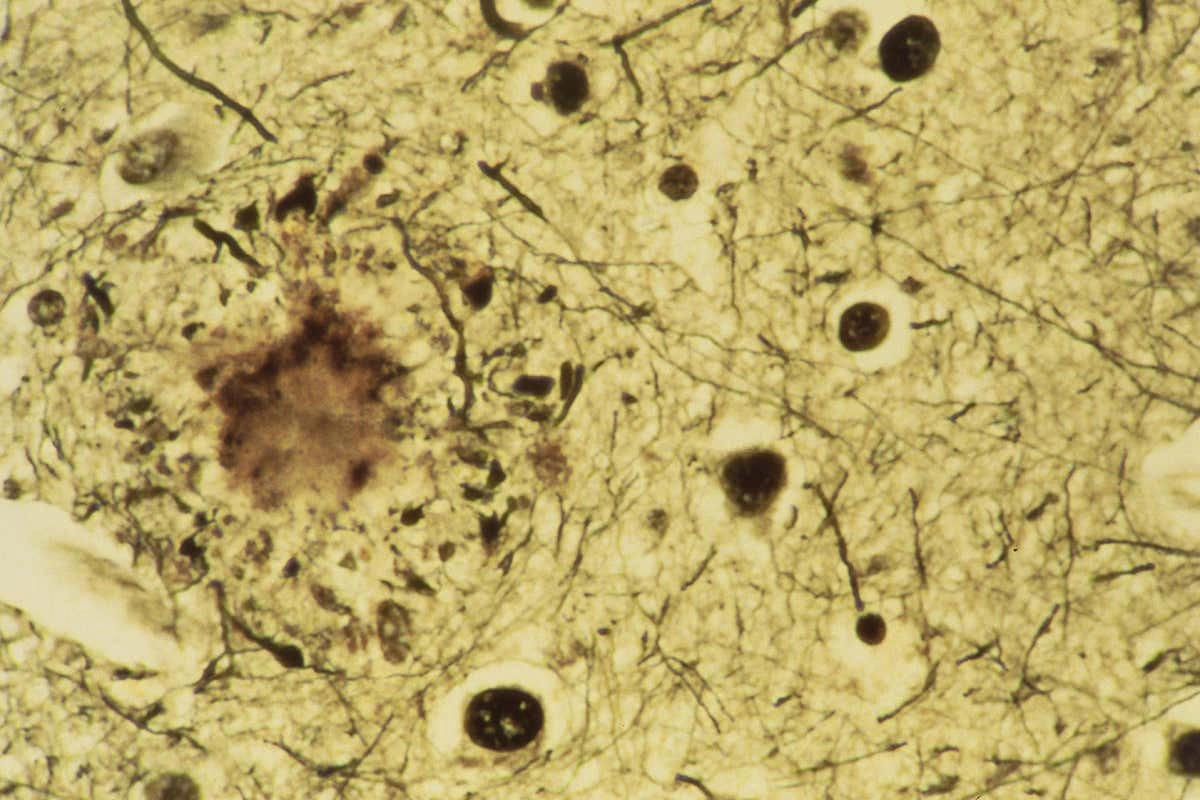

Несмотря на то, что ученые до сих пор не знают точной причины возникновения недуга, а также способов его лечения, известно, что бляшки в сосудах головного мозга играют центральную роль в развитии болезни.

Возможно, если устранить эти бляшки, прогрессирование болезни Альцгеймера замедлится. Такие бляшки возникают из-за аномального накопления амилоидного белка.